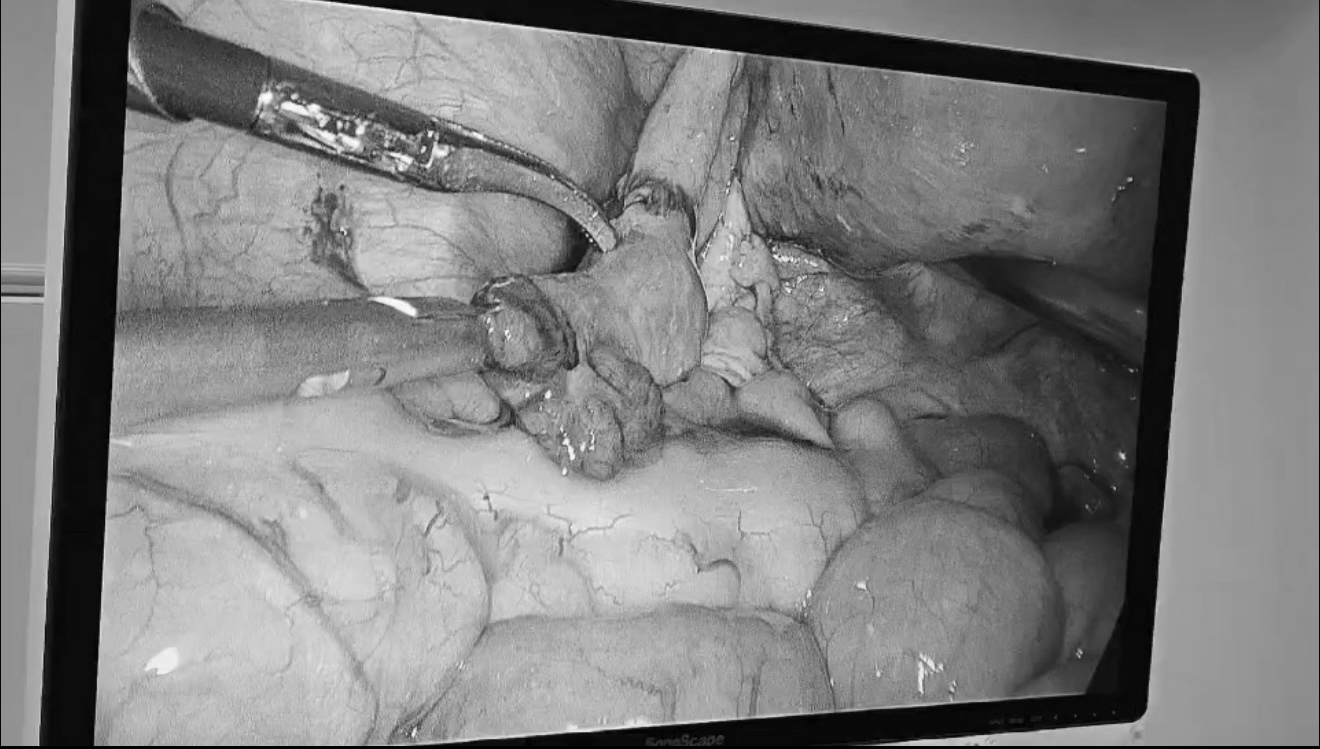

于近期顺利进行了腹腔镜下输卵管吻合+输卵管通液术,凭借先进的设备和精湛的技术,成功重建了输卵管的通畅性。术后患者恢复良好,对治疗效果充满期待。

1、高清腹腔镜可将手术视野放大4-10倍,能够清晰显示纤细的输卵管结构。

2、医生在屏幕上进行“显微”级别的精细操作,使用比头发丝还细的可吸收缝线进行分层吻合,极大提高了输卵管解剖结构和功能恢复的精准度。

术中可同步、直观地检查子宫、卵巢、盆腔及对侧输卵管的情况,及时发现并处理可能存在的子宫内膜异位症、盆腔粘连等问题,一次手术解决多个隐患。